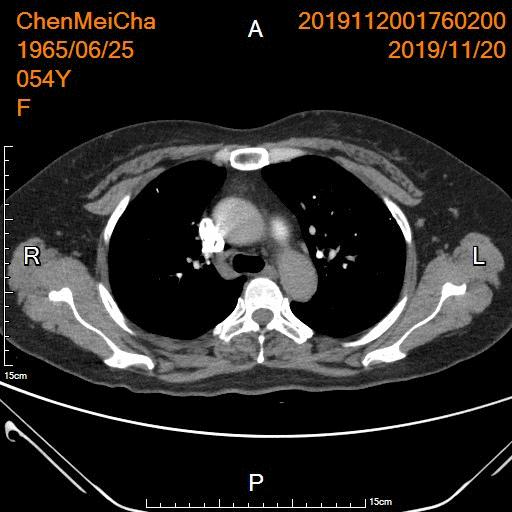

2周后复查肺动脉显示肺动脉血栓已清除

2周后复查肺动脉显示肺动脉血栓已清除;下肢静脉彩超未见血栓形成,血液回流顺畅。

术后2周顺利取出下腔静脉滤器,术后口服抗凝治疗3个月治疗。